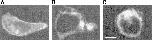

Figure 5. Imaging of GFP-tagged GABRG2 expressed with GABRA1 and GABRB2 subunits, revealing the fate of GABRG2Q351X-containing receptors in HEK293 cells. Images were obtained by confocal fluorescence microscopy (excitation, 488 nm; emission, >515 nm). The scale bar in panel C corresponds to 5 microns and applies to all three panels. A, EGFP-tagged wild-type GABRG2 subunit, found in both the membrane and the intracellular compartment (n=20 individual cells analyzed). B, EGFP-tagged GABRG2Q351X, found only in the intracellular compartment (n=20 individual cells analyzed). C, ER-targeted EYFP expression, demonstrating subcellular distribution of ER that is remarkably similar to that seen in B.